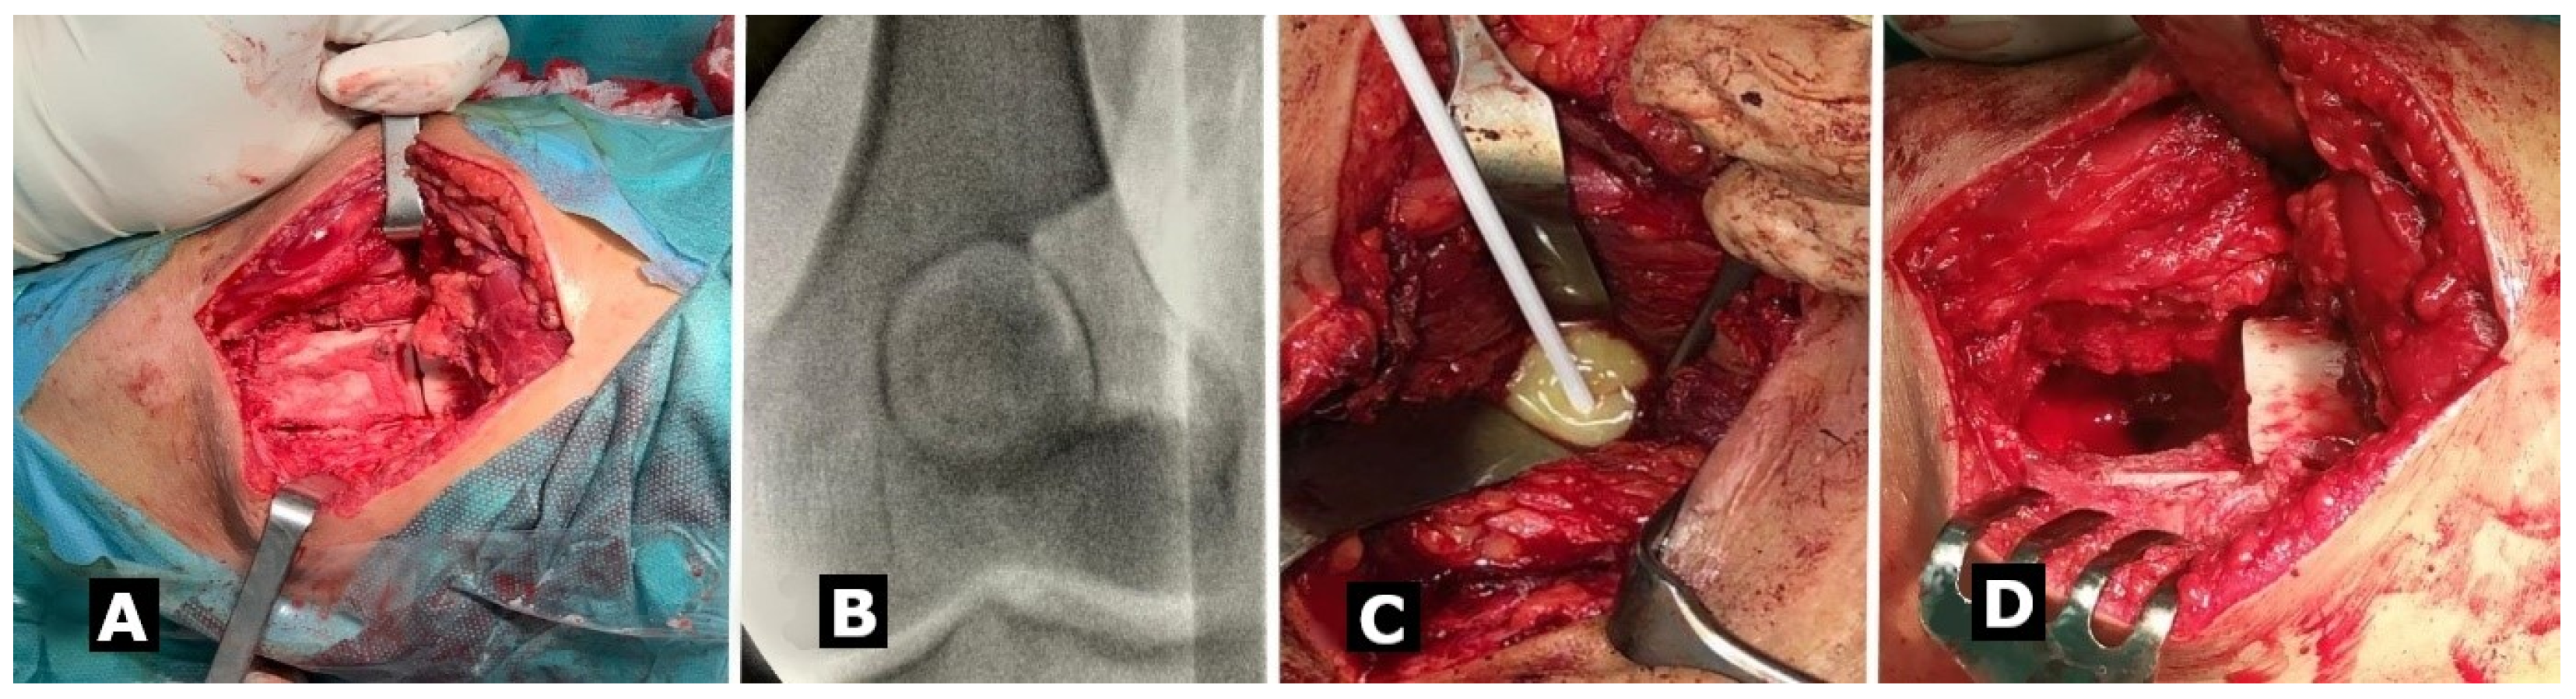

2. Materials and Methods

3. Management and Outcome